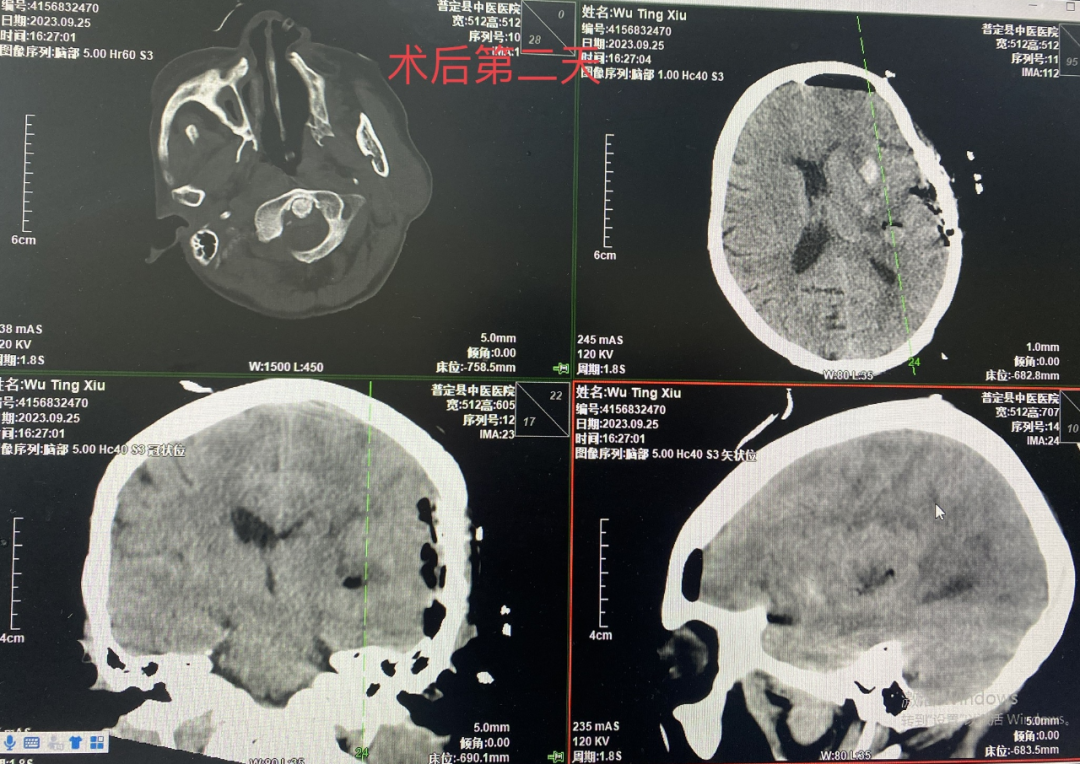

经过充分的术前讨论,制定详细手术方案,完善术前检查后,为患者行小切口小骨窗开颅血肿清除术,术中予避开神经功能区颞中回皮质造瘘长约1.5cm,深约1.5cm见血肿,术中减少脑组织牵拉,精准止血,减少电刀灼烧,清除血肿满意后还纳骨瓣,麻醉复苏后患者意识清醒,安返病房。术后6小时复查头颅CT提示血肿清除,未见颅内继发出血,血肿腔周围无明显水肿,手术效果良好,在科室医务人员的精心照顾下,患者日渐好转,于近日出院。

术后第二天CT